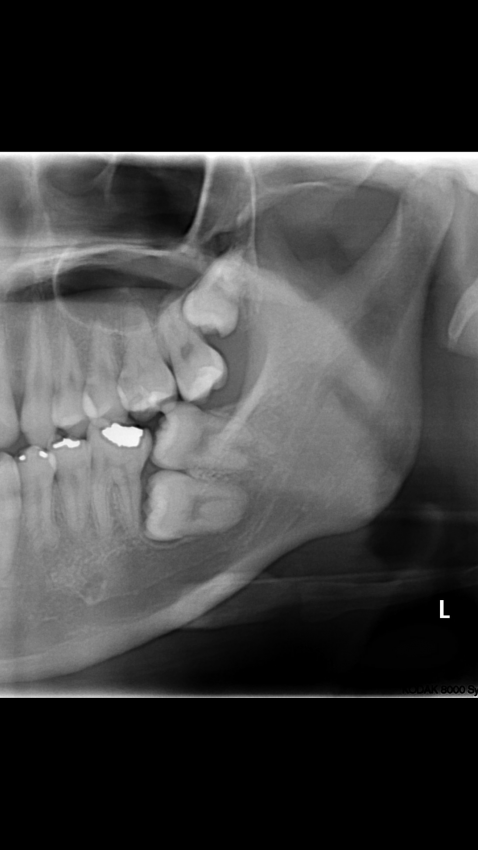

이중 매복 사랑니